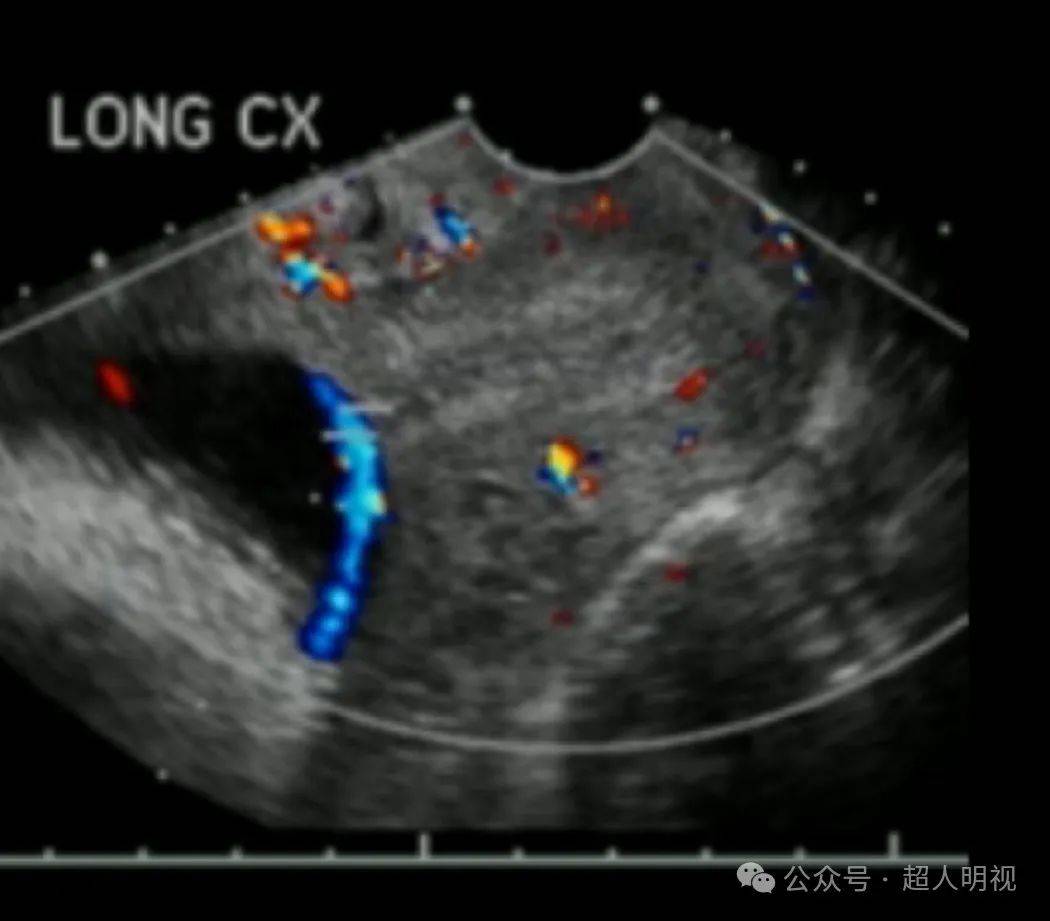

箭头指向宫颈内口,h 示胎儿头部图 4 经腹超声检查显示血管前置.

图片尺寸600x408